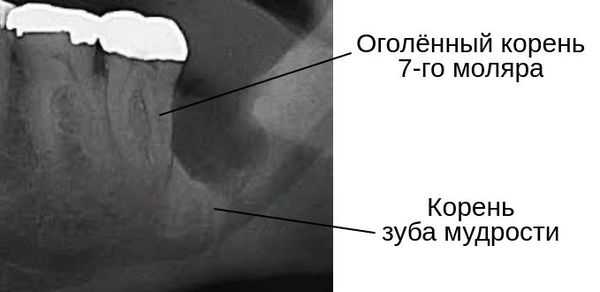

В запущенных случаях из-за возникшего кариеса может разрушиться корень соседнего зуба [14] . А при полном разрушении костной межальвеолярной перегородки между зубом мудрости и вторым моляром после удаления зуба мудрости обнажается часть корня седьмого зуба — возникает рецессия десны.